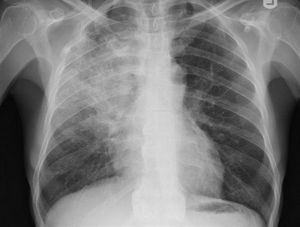

Pulmón

Mi pulmón